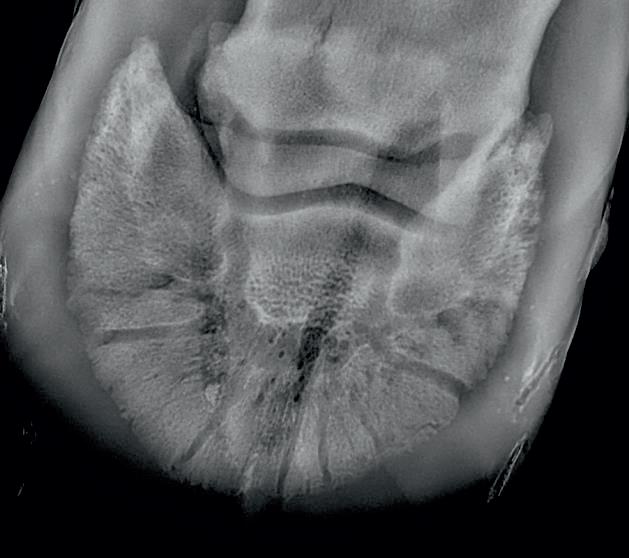

Radiographic proof in clinical results

BONE Gold nutritional bone joint and collagen supplement was formulated to provide some of the essential amino acid requirements of collagen type I, II and III (found in bone and connective tissue) in addition to supporting the nitric oxide pathway which has been found to assist in the formation of bone callus postinjury.

Here is a veterinary radiographic report on a horse with a fracture evident on the medial toe and after treatment and feeding Bone Gold during this period. More information on these products can be found at www.vetgold.com.au

VETERINARY RADIOGRAPHIC REPORT

HORSE: "XXXXXXXX"

DATES OF EXAMINATION: 26TH AUG, 21ST OCT 21 & 17TH NOV '21

HORSE: “XXXXXXXX”

PLACE: XXXXXXXXXX FARM

DATES OF EXAMINATION: 26TH AUG, 21ST OCT 21 & 17TH NOV ‘21

XXXXXXX's left and right front feet were radiographed on 26th Aug, 21st Oct (8 weeks) and again on the 17th Nov '21(12 weeks).

XXXXXXX’s left and right front feet were radiographed on 26th Aug, 21st Oct (8 weeks) and again on the 17th Nov ‘21(12 weeks).

RADIOGRAPHS:

26.08.21: Right Front: Large P3 solar margin fracture evident on medial toe 32.6mm x 4.1mm with approximately 1.4mm separation from parent bone as below left image.

21.10.21: Right Front: Fine residual 4.2mm fracture still evident, approximately 90% resolution

17.11.21: Right Front: Fracture fully resolved

26TH AUG 21

21ST OCT 21

Radiographic results as of the 17th Nov '21 show total resolution of the original fracture.

XXXXXXX was reshod today utilising off an alloy shoe with a toe clip - inner circumference seated out to avoid any sole pressure. The horse can return to training.

Please do not hesitate to contact me if you have any further queries

COMMENTS:

Solar margin Type IV fractures of this magnitude have well-documented internationally published healing rates of 7 - 12 months. Full resolution of these fractures is rare as most often the fracture fragments are resorbed. Full resolution in a 3 month period was not anticipated.

The horse was on Bone Gold 3 x scoops fed once per day for this period.

26th August 2021 21st October 2021 17th November 2021